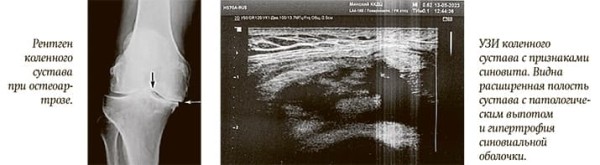

В отличие от рентгеновского исследования, на котором оценивается в основном только состояние костной ткани, ультразвук чувствителен к воспалительным процессам. Бывает, что пациент жалуется на боль и распухший сустав, и даже визуально это заметно, но рентген не показывает изменений.

В таком случае УЗИ дает дополнительную информацию и позволяет поставить верный диагноз. Мы можем увидеть признаки острого или хронического синовита, сделать вывод о наличии патологического количества внутрисуставной жидкости, выявить кисты Бейкера, определить начальные признаки дегенеративных процессов.